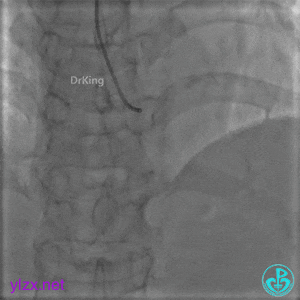

PL远端血管周围似乎有片状造影剂滞留。

经微导管PL分支造影,该如何解读这个经微导管造影结果?

经微导管造影。

远段造影剂外渗在增加,怎么办?